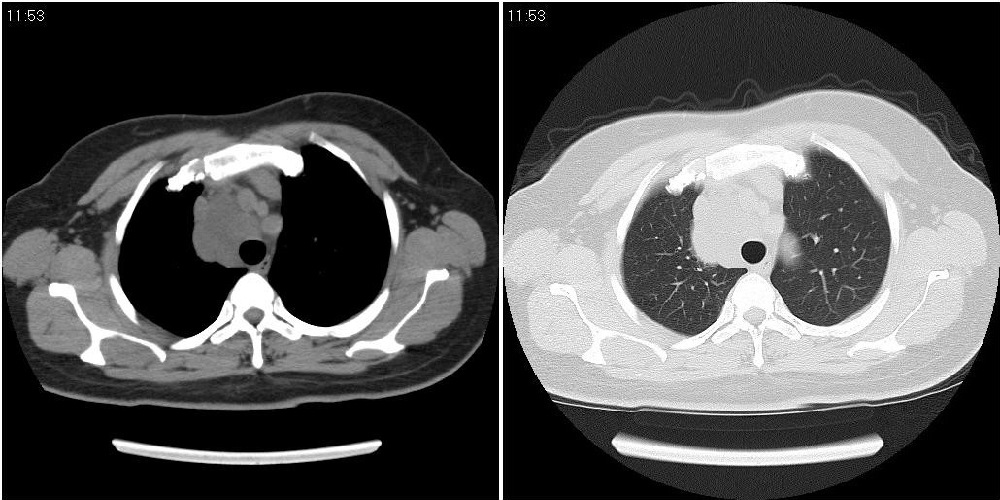

标题: CT24795:女性,47岁,右下腿静脉静脉曲张手术前体检,发现 [打印本页]

标题: CT24795:女性,47岁,右下腿静脉静脉曲张手术前体检,发现

囊性无明显占位效应:1淋巴管囊肿2畸胎瘤(其上部见小钙化)3前肠囊肿

右上纵隔囊性占位性病变;考虑淋巴管囊肿,不排除支气管囊肿。

支气管囊肿、囊性畸胎瘤、肠源性囊肿均有可能。

右上纵隔囊性占位性病变;考虑淋巴管囊肿,不排除支气管囊肿。 建议增强。

考虑淋巴管囊肿,不排除前肠囊肿。